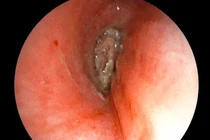

hat-hong-xiem1.jpg

Hạt hồng xiêm được lấy ra - Ảnh BVCC